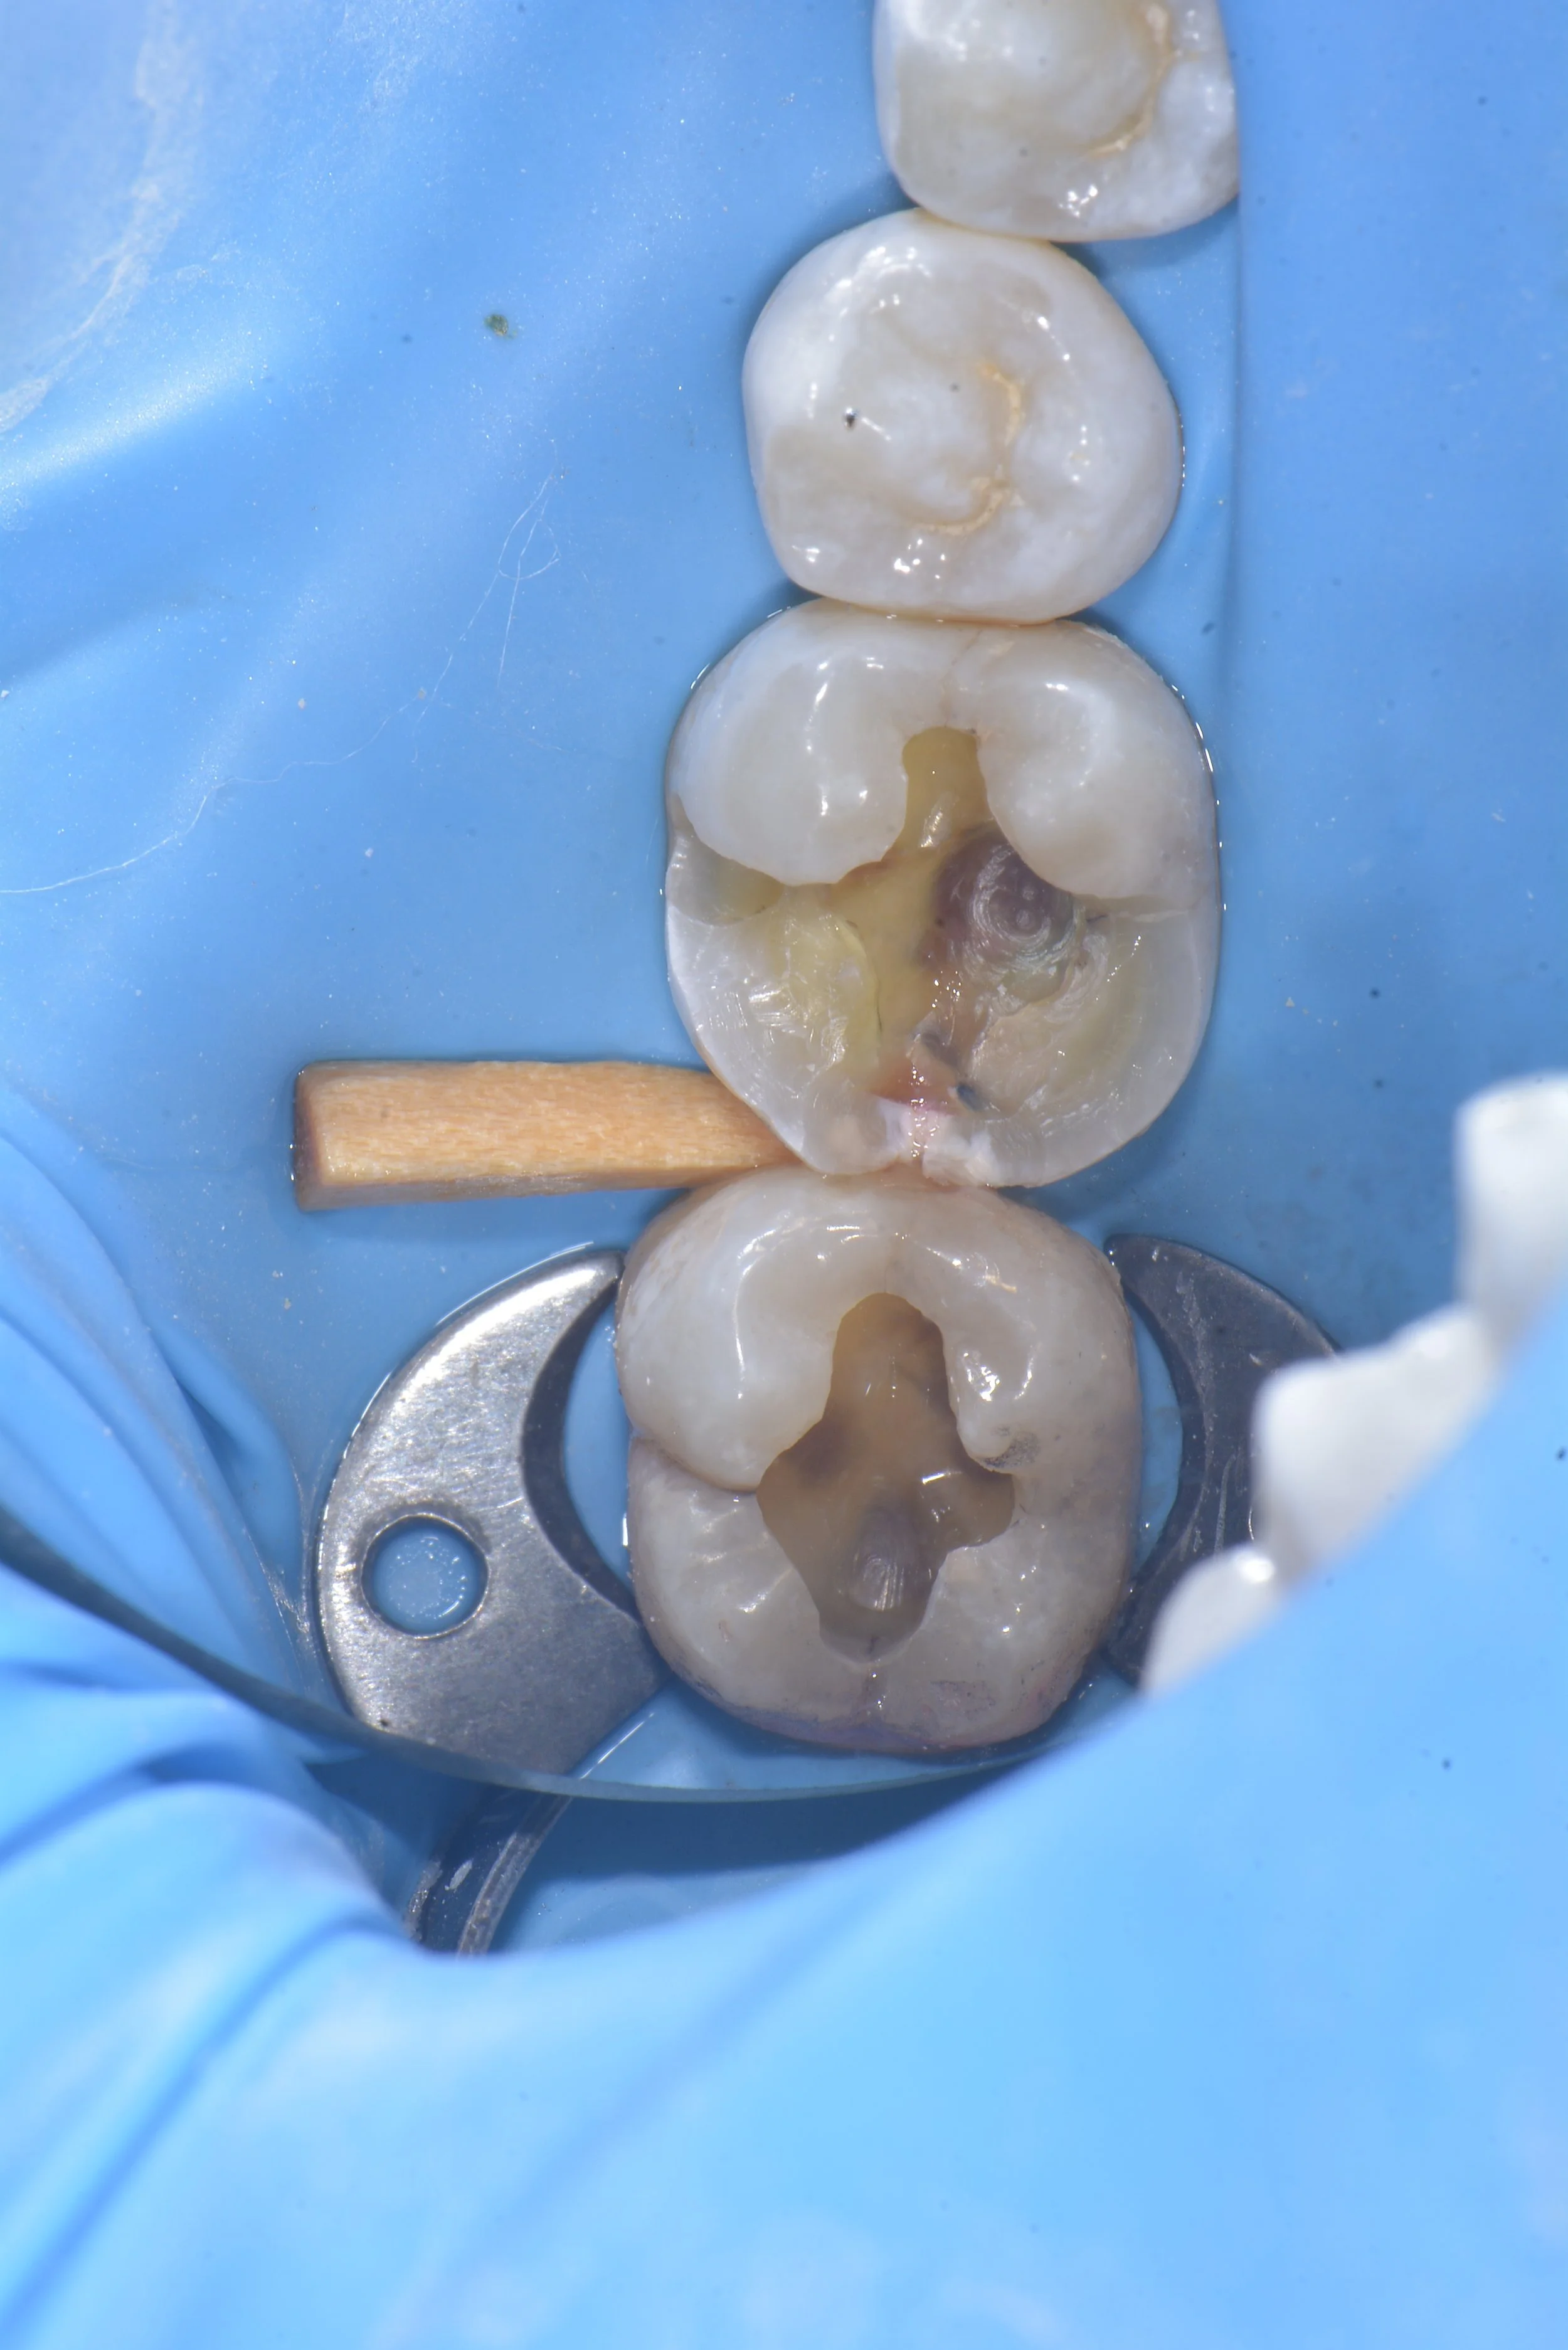

Occlusal effect caries is caused by peripheral rim fractures that create a pathway for bacteria to enter into the tooth and create a carious lesion. Occlusal effect caries is distinguished by its symmetric shape around the peripheral rim fracture.

This case by Dr. Davey Alleman, DMD shows how peripheral rim fractures can be treated and the teeth restored with biomimetic protocols to conserve the remaining tooth structure.

Peripheral rim fractures are often visible from staining in the crack. Use high magnification of at least 6.5-8x magnification for diagnosis. Carious lesions that are symmetrical around the crack are considered occlusal effect caries and having originated from the peripheral rim fracture.  These lesions will stain with caries detector dye but in the initial stages are not visible on x-rays.

These photos by Dr. Davey Alleman, DMD show how a carious lesion forms around a peripheral rim fracture. This lesion is called occlusal effect caries.